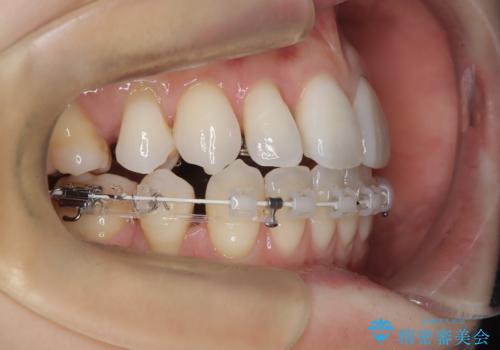

ハーフリンガル矯正|上下4本の抜歯で叢生を改善し、美しい歯並びへ

- 患者様は、歯並びの乱れ(叢生)を整えたいが、前歯の突出感は気にならないとのことで来院されました。診察の結果、全体的な歯列のスペース不足により抜歯が必要と判断。しかし、前歯を大きく下げる必要はなかったため、小臼歯の中でも5番(第二小臼歯)を抜歯する治療計画を立てました。装置は、上顎が舌側(リンガル)、下顎が表側(審美ワイヤー)のハーフリンガル矯正を採用し、目立ちにくさと効率的な歯の移動を両立しました。

抜歯によって歯を並べるためのスペースを確保。その後、ハーフリンガル矯正を用いて、上顎は舌側から、下顎は目立ちにくいワイヤーで歯を誘導し、歯列全体を整えました。治療期間を通じて、噛み合わせのバランスも改善し、機能的にも審美的にも理想的な仕上がりとなりました。患者様からは「目立たずに矯正でき、きれいな歯並びになって嬉しい」とご満足いただきました。